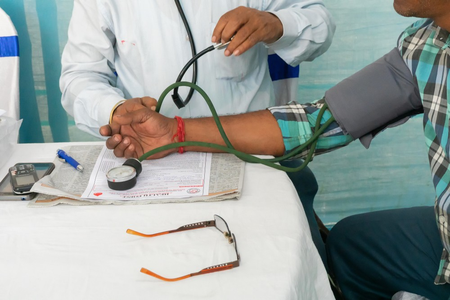

शरीर में बीमारियों का 'जनक' हाई बीपी, छोटी-छोटी बातों का रखना होगा ध्यान

शोध : हाई ब्लड प्रेशर के मरीजों में असरदार है ये नई दवा

शोधकर्ताओं ने बनाया नया ऑनलाइन टूल, उच्च रक्तचाप के इलाज में करेगा मदद